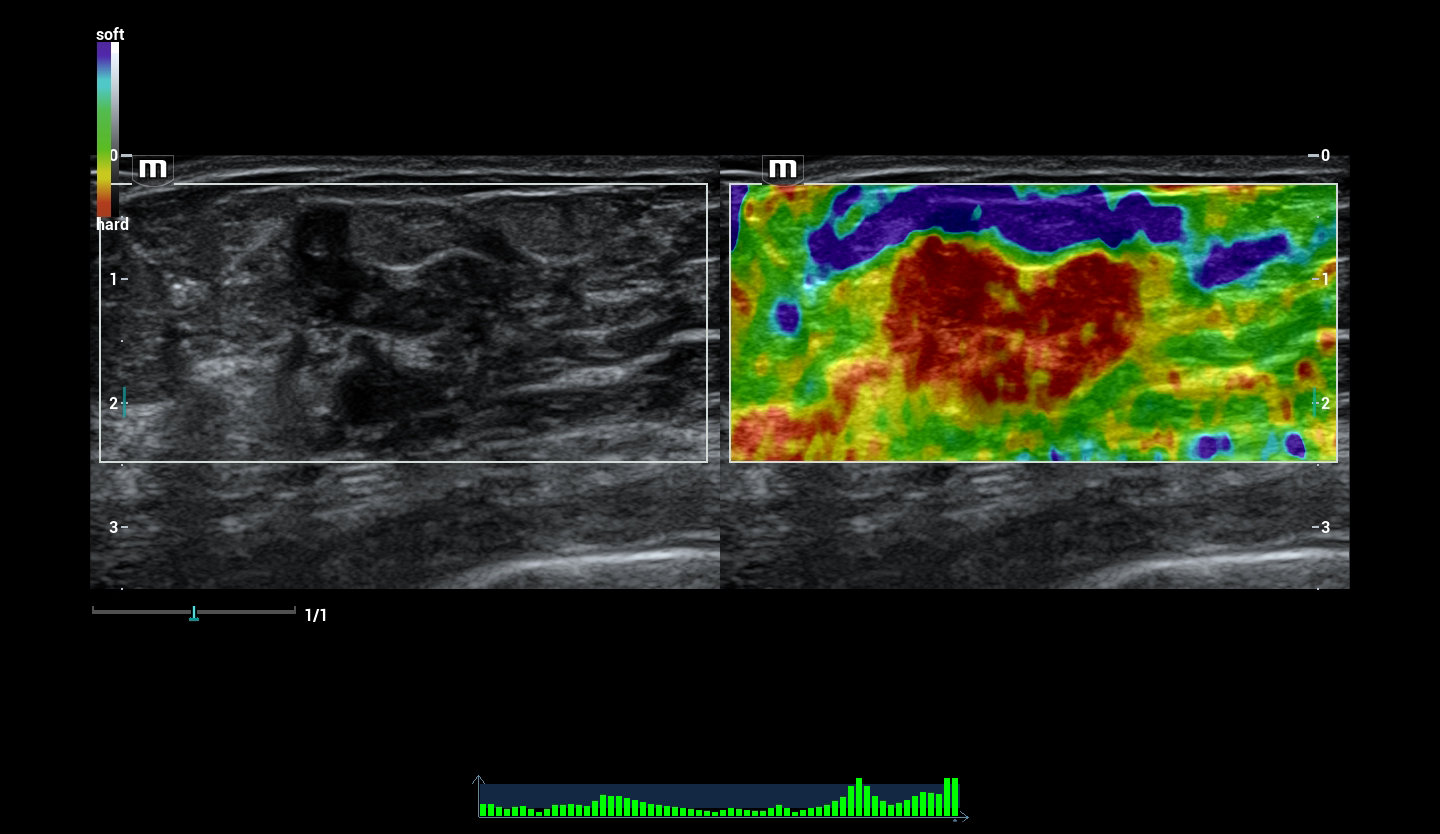

-HiFR STE - инновационная оценка жесткости. В 10 раз более высокая частота кадров при работе режима STE. Более чувствительное обнаружение движения для лучшей стабильности и большей точности.